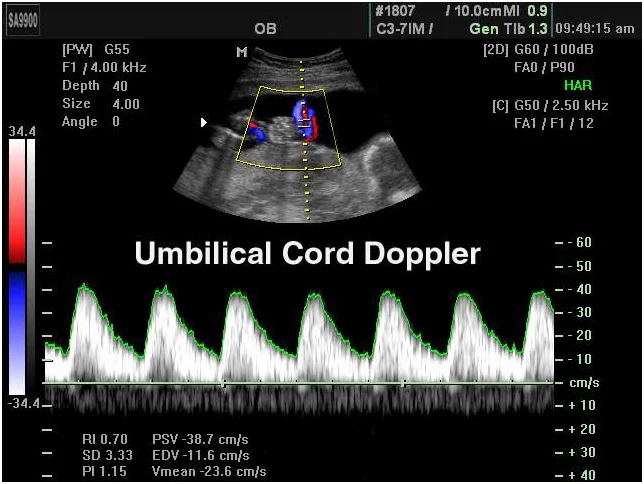

Umbilical Artery

Monitors the essential blood flow traveling from the placenta to the baby.

Fetal Doppler Scan Report - Jammi Scans

See what our comprehensive Fetal Doppler scan reports look like.

A fetal Doppler scan is used to assess blood flow between the mother, placenta, and baby.

- Umbilical artery PI/RI

- MCA Doppler for anemia risk

- Uterine artery notching

- Combined with Growth Scan